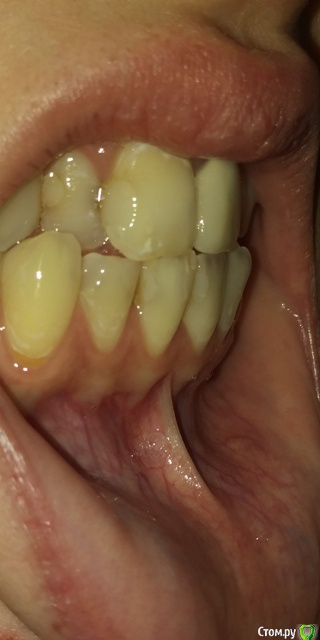

Есть рецессии на нижних зубах и на верхнем клыке слева и резорбция. Ортодонты говорят, что это последствия неправильного прикуса, травмирующего смыкания и с брекетами все стабилизируется, но из-за движения зубов может и усугубиться, как повезет. Вестибулопластику никто не предлагал, а один вообще сказал, что в моем случае она бесполезна. У хирурга-парадонтолога другое мнение: нужно сделать сначала операцию на нижних зубах (углубить преддверие, устранить тяжи и положить какой-то там замещающий материал), а потом поставить брекеты, иначе без операции брекеты спровоцируют еще большее оголение и рецессии станут просто огромными.  А после брекетов уже закрывать, если нужно, рецессии.  Прошу поделиться вашим мнением? В чем причина рецессий и резорбции? Поможет ли в моем случае вестибулопластика?